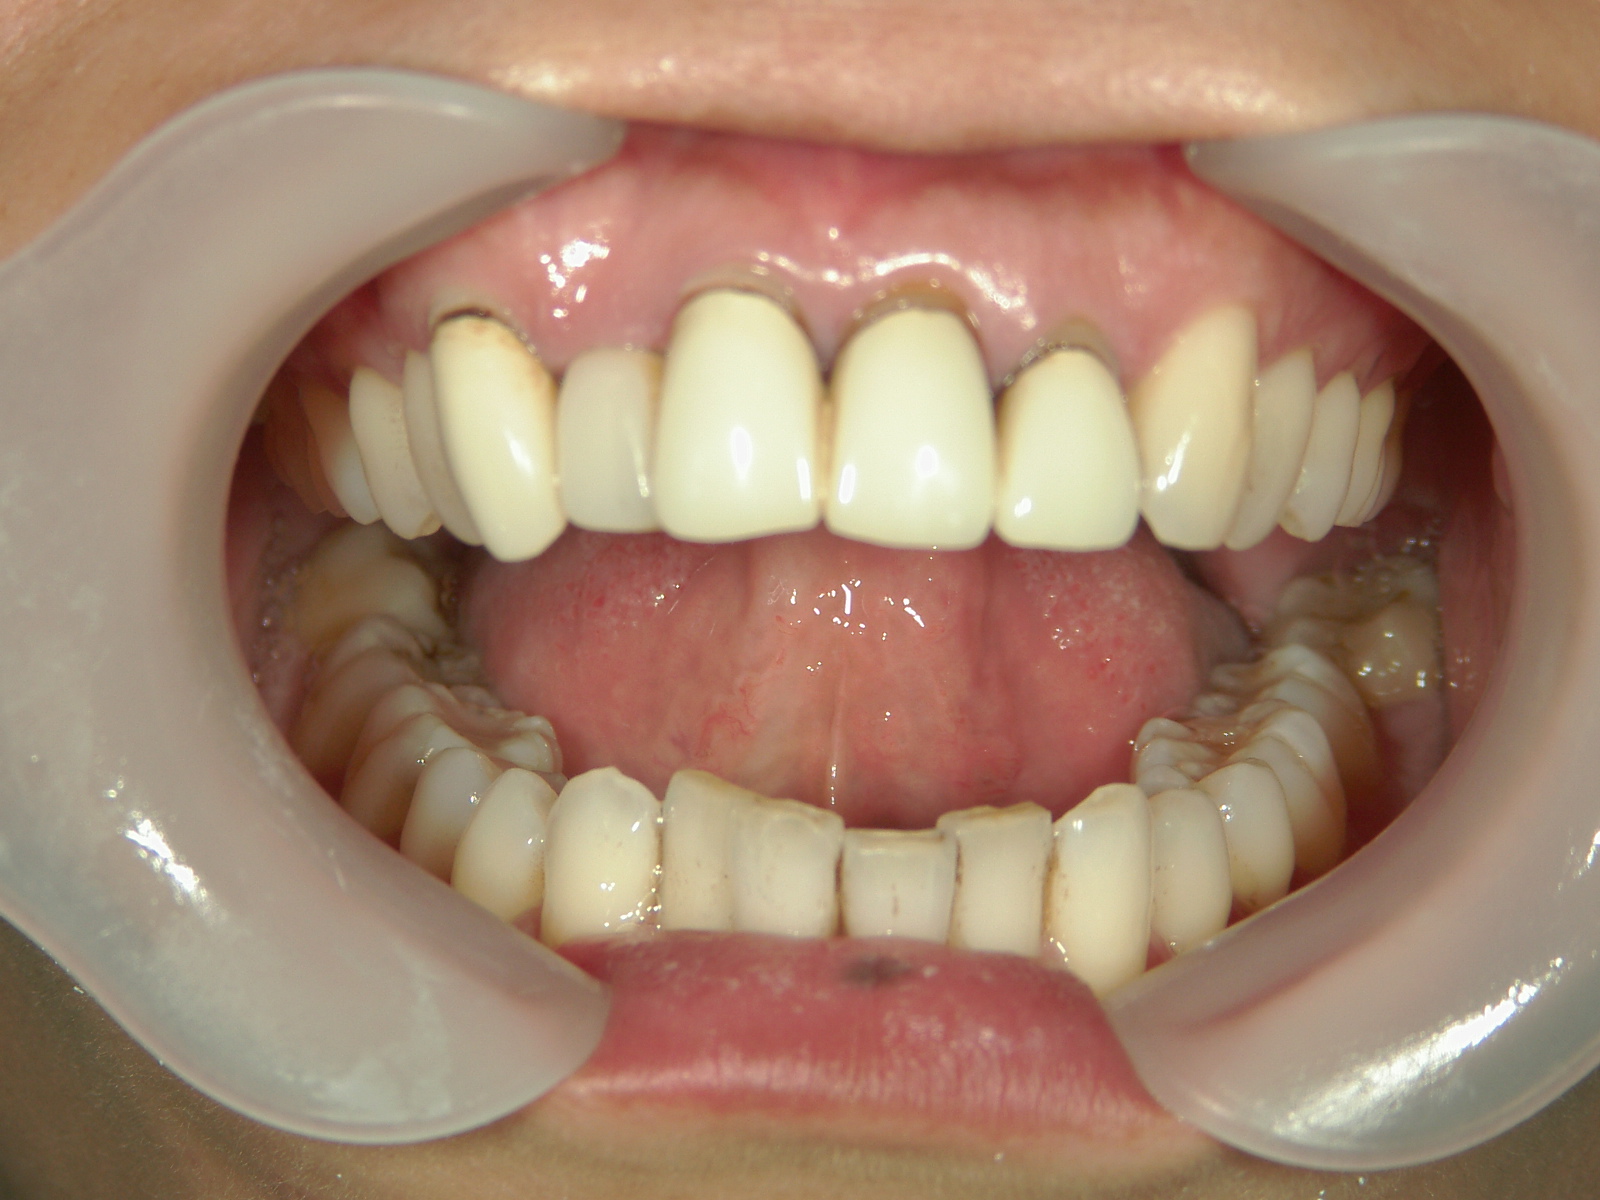

全顎ワイヤー矯正 症例(82)

主訴: 前歯の歯並びが気になる。

上下左右 第一小臼歯(4本)、左右上 親不知(2本)を抜歯。

ミニインプラント、アップライトスプリングを併用。

矯正前に左右上前歯4本を仮歯に変え、矯正治療後にセラミック(SHT)に冠せなおしました。

カテゴリー : ガタガタ(叢生)